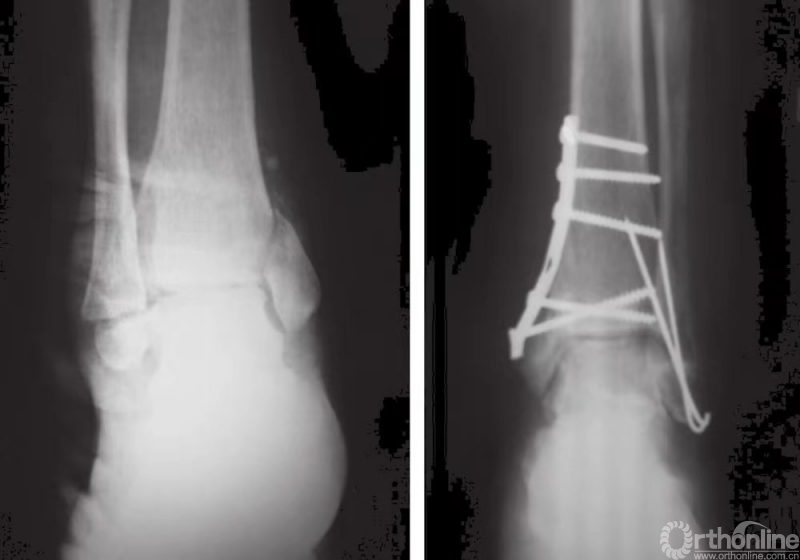

当发生内侧压缩时,可能还需要进行骨移植。如果内侧骨折片非常小,则固定时可用一枚螺钉和一枚克氏针或用两枚遵循静态张力带原理的克氏针(图20和图21)。

图20 旋后内收型踝关节骨折,内踝可用支撑钢板固定,外踝可用长克氏针固定。

图21 内侧骨折片非常小,则固定时可用一枚螺钉和一枚克氏针或用两枚遵循静态张力带原理的克氏针